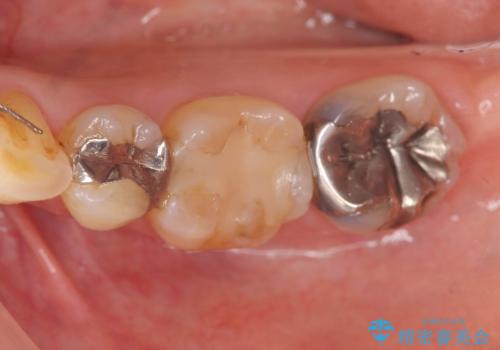

破折歯のインプラント治療、奥歯の根管・セラミック治療